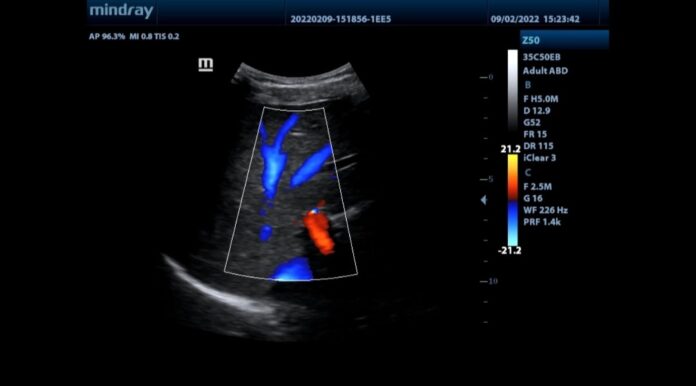

Și cum serviciile medicale la domiciliu reprezintă una din direcțiile de dezvoltare, am achiziționat un ecograf portabil modern, performant, cu sondă convexă și liniară multifrecvență, cu doppler color și pulsat.

Putem efectua acum la domiciliul pacientului atât ecografii clasice, abdominale, cât și ecografii de părți moi (hematom, abces), doppler carotidian (stare post accident vascular) doppler venos (pacient imobilizat cu risc de tromboză venoasă profundă) sau doppler arterial (ischemie cronică sau acută de membru inferior).”, transmite clinica Justilmed.